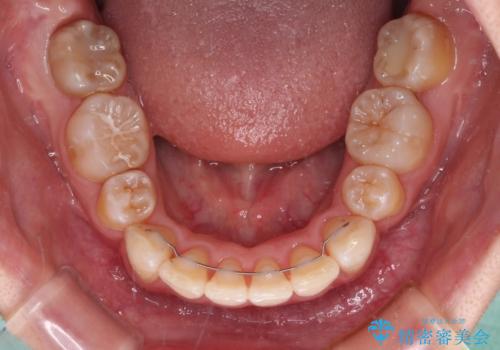

飛び出した前歯を引っ込めたい 目立たないワイヤーでの抜歯矯正

- 口元の閉じにくさと、前歯のでこぼこの歯並びを気にして来院された患者様です。

口元を積極的に引っ込めるために、上下左右の小臼歯計4本を抜歯することとしました。

咬み合わせが深く、咬合力強いため、補助装置を使用しながら積極的に口元を下げることとしました。